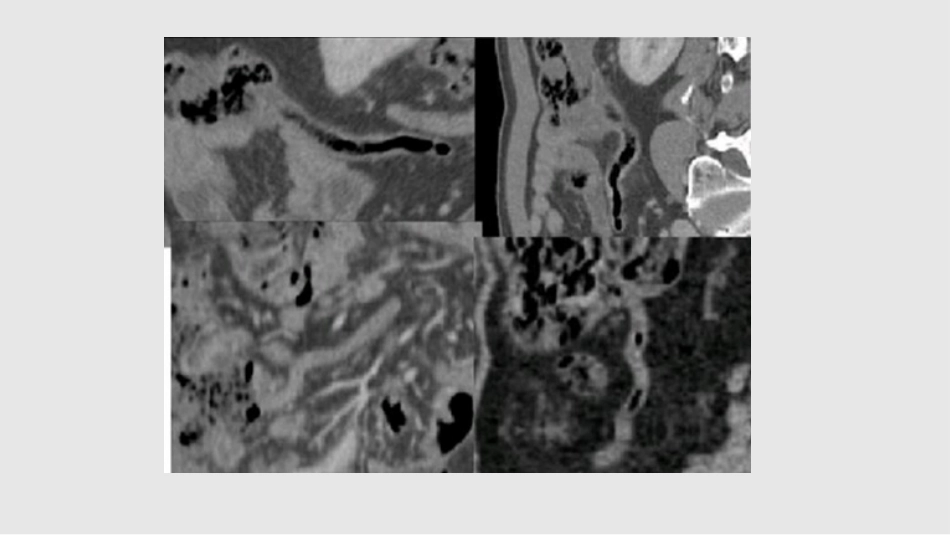

阑尾炎CT诊断遵义市第一人民医院影像科黄清附属于盲肠的一段肠管,形式蚯蚓,又称蚓突阑尾根部连接于盲肠后内侧壁,远端游离,位置随盲肠位置而定。1.左位阑尾2.高位阑尾3.腹膜外阑尾4.疝内阑尾(位于腹外疝囊内)5.壁内阑尾6.腔内阑尾7.低位阑尾8.错位阑尾长度:6-8cm管壁:≤3mm位置:常位于右侧髂窝、回盲瓣下3cm,以盲肠后位及回肠后位多见内可见气体(20%)、液体(4%)、混杂密度(58%),约18%塌陷1.节段性阑尾2.阑尾憩室3.阑尾过长>20cm4.短小阑尾<1cm5.阑尾缺如发育异常阑尾血供急性阑尾炎是外科常见病,居各种急腹症首位它可发生在任何年龄,以青少年多见,20-30岁年龄组为高峰,约占总数的40%。男:女=2:1~3:1。阑尾管腔梗阻淋巴滤泡的明显增生,约80%粪石阻塞,约35%异物、炎性狭窄、食物残渣、蛔虫、肿瘤细菌入侵革兰阴性杆菌厌氧菌胃肠道影响阑尾管壁肌痉挛,血运障碍以感染和梗阻为主病理类型急性单纯性阑尾炎病变早期,限于粘膜和粘膜下外观—轻度肿胀,浆膜充血,失去正常光泽,表面少量纤维素性渗出镜下—阑尾各层水肿,中性粒细胞浸润,粘膜表面小溃疡和出血点临床症状和体征较轻急性化脓性阑尾炎(蜂窝组织炎)由单纯阑尾炎发展而来外观—肿胀明显,浆膜高度充血,表面覆盖以纤维素性(脓性)渗出物镜下—阑尾粘膜溃疡面加大达肌层,管壁各层小脓肿形成,腔内积脓临床症状和体征较重局限性腹膜炎形成急性坏疽性阑尾炎病变进一步加剧外观—呈暗紫色或黑色镜下—阑尾管壁坏死或部分坏死,阑尾腔内积脓,压力升高2/3病例发生穿孔,多位于根部和阑尾近端急性弥漫性腹膜炎临床症状和体征重急性阑尾炎伴周围脓肿形成急性化脓性阑尾炎急性坏疽性阑尾炎急性阑尾炎伴穿孔大网膜移至右下腹阑尾包裹并形成粘连炎性肿块周围脓肿急性阑尾炎CT征象1.盲肠、升结肠充气:但不扩张,又是末端回肠充气,放射性肠淤积。2.阑尾增粗(管腔直径>10mm):使用长对比剂时,如阑尾被肠道对比剂或气体完全充盈,则可排除阑尾炎诊断。3.阑尾周围炎:急性阑尾炎患者98%出现阑尾周围炎,表现为脂肪线型侵润,局部筋膜增厚、系膜密度增高。4.阑尾粪石:非特异性征象,如仅显示粪石但无扩张及周围炎性改变,不可诊断阑尾炎。5.CT增强检查:阑尾炎症时可弥漫或首先累及粘膜及粘膜下层,引起阑尾、盲肠或邻近末端回肠肠壁增厚,强化均匀或不均匀,盲肠壁增厚分层称靶征。6.阑尾炎穿孔的征象直接征象阑尾壁不连续—增强扫描阑尾腔内粪石或对比剂外漏间接征象阑尾周围游离气体蜂窝织炎脓肿形成特殊类型阑尾炎1.新生儿急性阑尾炎2.小儿急性阑尾炎3.妊娠期急性阑尾炎4.老年急性阑尾炎谢谢